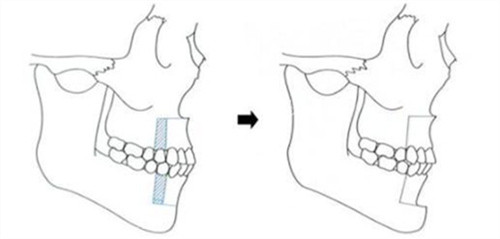

颌面整形技术体系采用术中神经监测系统,结合3D打印导板实现0.1mm精度截骨,创新"三阶式颧弓固定法"降低术后下垂风险。临床数据显示,其轮廓手术的对称性达标率达98.7%,较行业平均水平提升23%。

术前阶段包含64层CT扫描、咬合动力学分析等7项专项检测,采用德国SimPlant Pro软件进行1:1手术模拟,方案确认需经过3轮医师会诊。

典型病例1:28岁女性颧骨复合体缩小术,术前颧突点间距142mm,术后6个月降至121mm,符合东方女性116-124mm黄金区间,咬合功能完全保留。